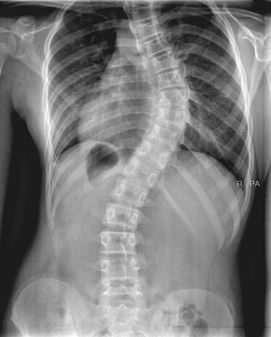

Importance  Adolescent idiopathic scoliosis, a lateral curvature of the spine of unknown cause with a Cobb angle of at least 10°, occurs in children and adolescents aged 10 to 18 years. Idiopathic scoliosis is the most common form and usually worsens during adolescence before skeletal maturity. Severe spinal curvature may be associated with adverse long-term health outcomes (eg, pulmonary disorders, disability, back pain, psychological effects, cosmetic issues, and reduced quality of life). Early identification and effective treatment of mild scoliosis could slow or stop curvature progression before skeletal maturity, thereby improving long-term outcomes in adulthood.

9826 AIS.jpg admin 08 May, 2018 14.02 Kb 1670